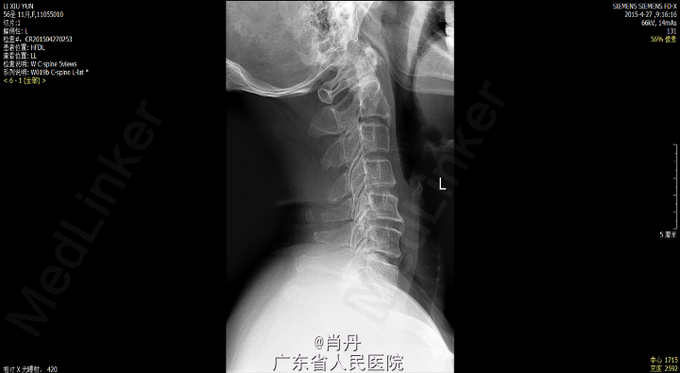

患者女,57岁,因“双上肢麻木8年加重伴双下肢行走不稳2年”入院。8年前开始出现双上肢麻木感,逐渐加重,一直未诊治,2年前开始出现行走不稳,行走踩棉花感,近几个月来不能独立行走,需要搀扶。入院临床诊断:脊髓型颈椎病。

查体双上肢皮肤触痛觉减退,四肢肌力正常,四肢肌张力增高,四肢病理征阳性,深反射亢进。X光CT,MR如下,C5~C6后纵韧带骨化,继续性颈椎管狭窄,相应平面脊髓变性。JOA 7 分(17分法)

诊断:脊髓型颈椎病,颈椎后纵韧带骨化症;处理:一期颈椎后路C3-7单开门,二期颈椎前路C5-6椎体次全切除。一期颈椎后路术后JOA由 术前的7分改善到11分,二期颈椎前路手术后改善到13分。